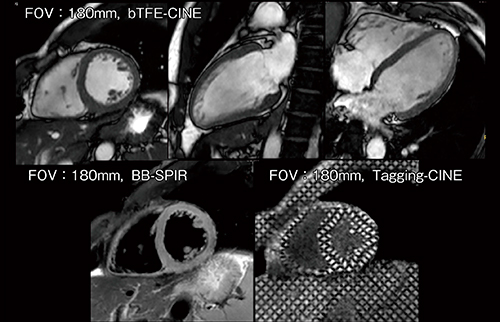

図3 Ingenia 3.0T CX(200mT/m/ms)によるWHCA

3.0T bTFE MRA,TR:4.7ms,TE:2.3ms,FA:70°

図5 Ingenia 3.0T CXによるdS Zoom Cardiac(FOV:180mm)

(画像ご提供:静岡県立静岡がんセンター様)